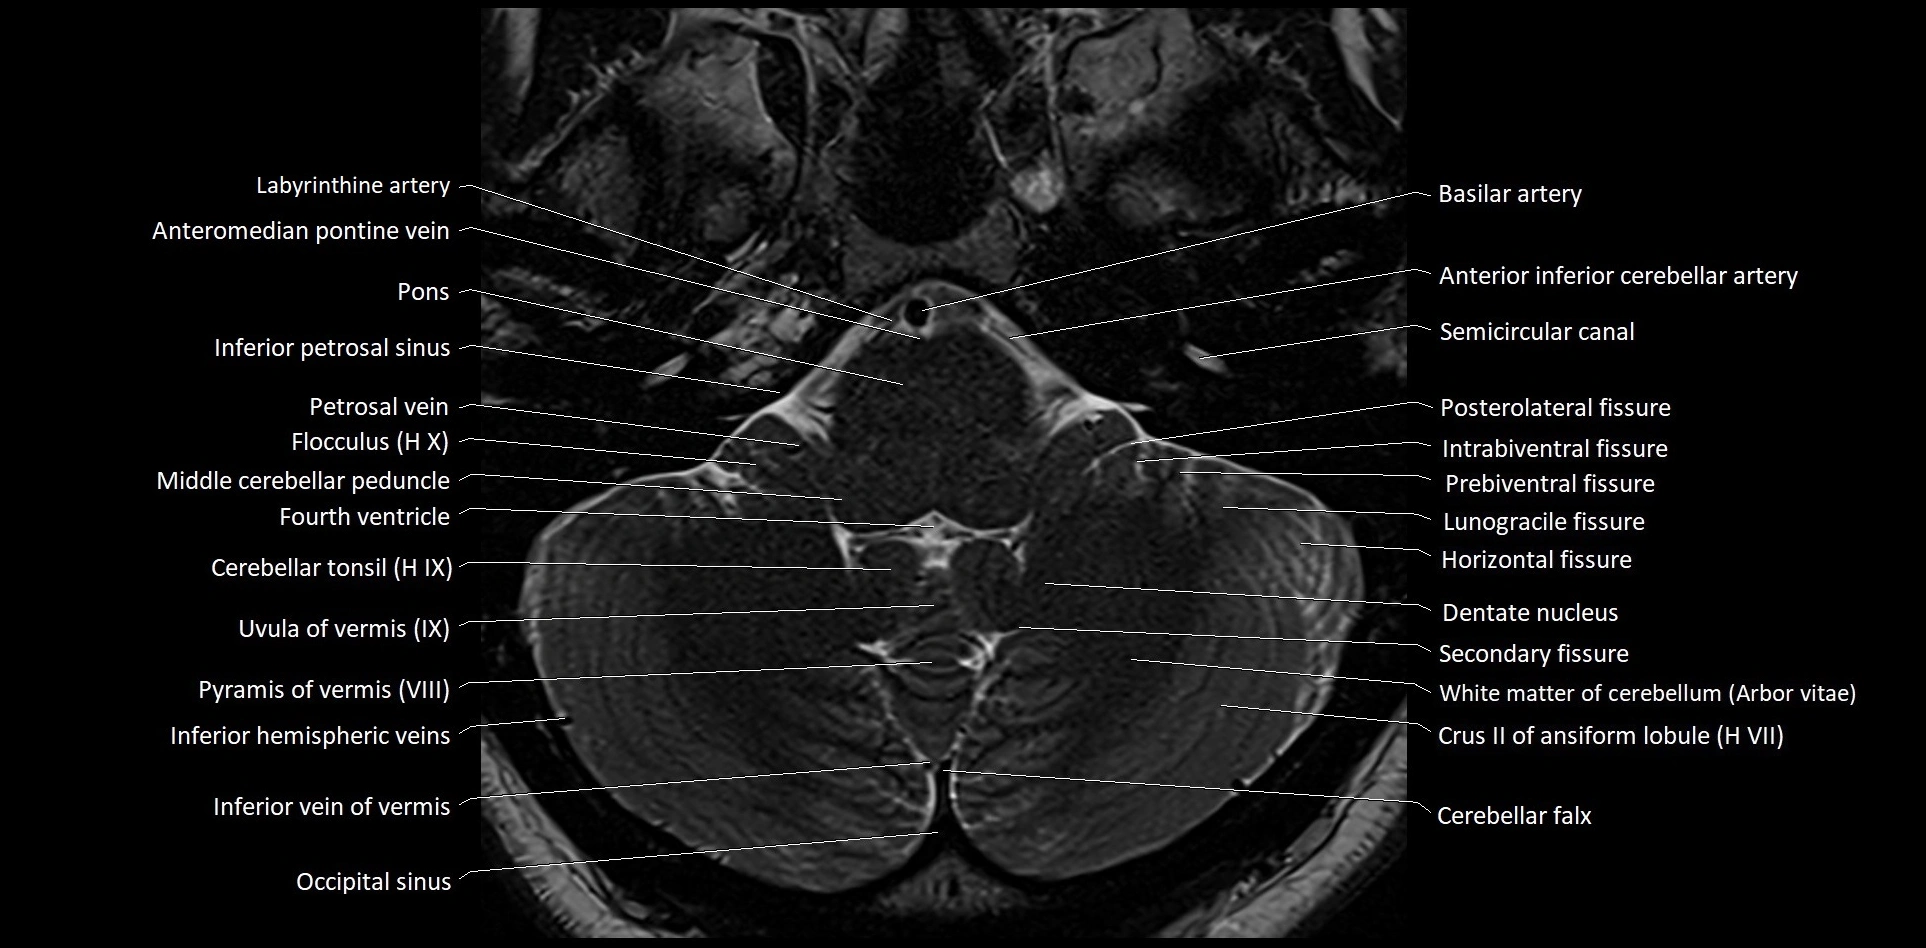

MRI images